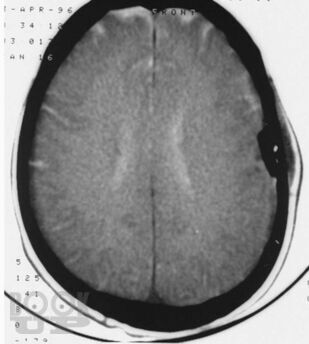

Учебное пособие написано в соответствии с основной профессиональной образовательной программой — программой подготовки кадров высшей квалификации в ординатуре по специальности 31.08.56 «Нейрохирургия». Издание содержит 144 ситуационные задачи. В задачах приводятся клинические случаи по всем разделам программы, в том числе рассматриваемые на смежных с нейрохирургией дисциплинах. Особое внимание уделено клиническим примерам, иллюстрирующим основные неотложные состояния у пациентов и раненых нейрохирургического профиля.

Ситуационные задачи составлены с целью обучения ординаторов методике диагностики травм и заболеваний нервной системы; также они могут быть актуальными и для практикующих нейрохирургов в качестве справочного пособия, в котором приведены алгоритмы диагностики и стандарты оказания помощи при наиболее распространенных нейрохирургических заболеваниях и травмах.